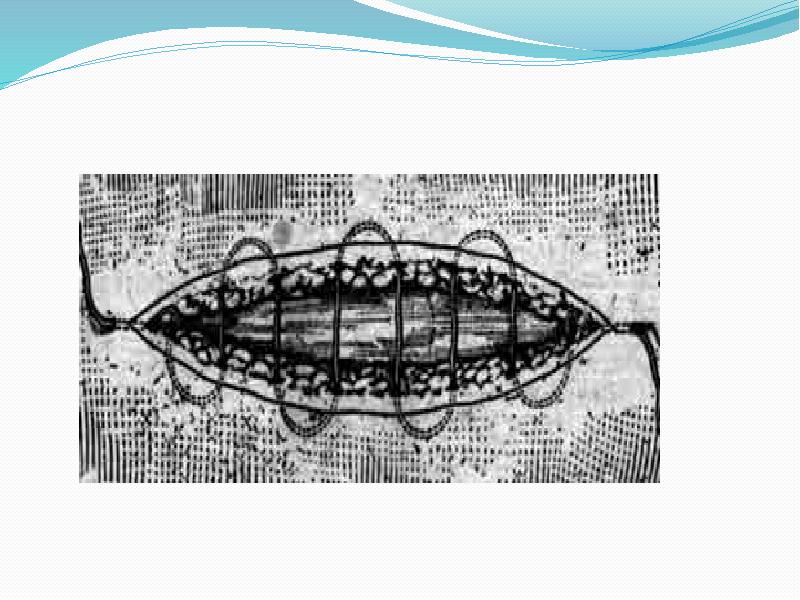

- 50. Внутрикожный непрерывный шов по Холстеду Шов начинают вблизи от угла раны,